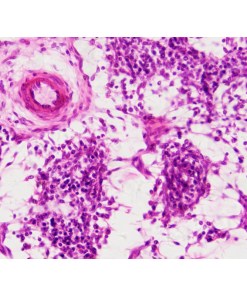

Microscop digital DTX 90

1 × 1,367.00 lei

Microscop digital DTX 90

1 × 1,367.00 lei -